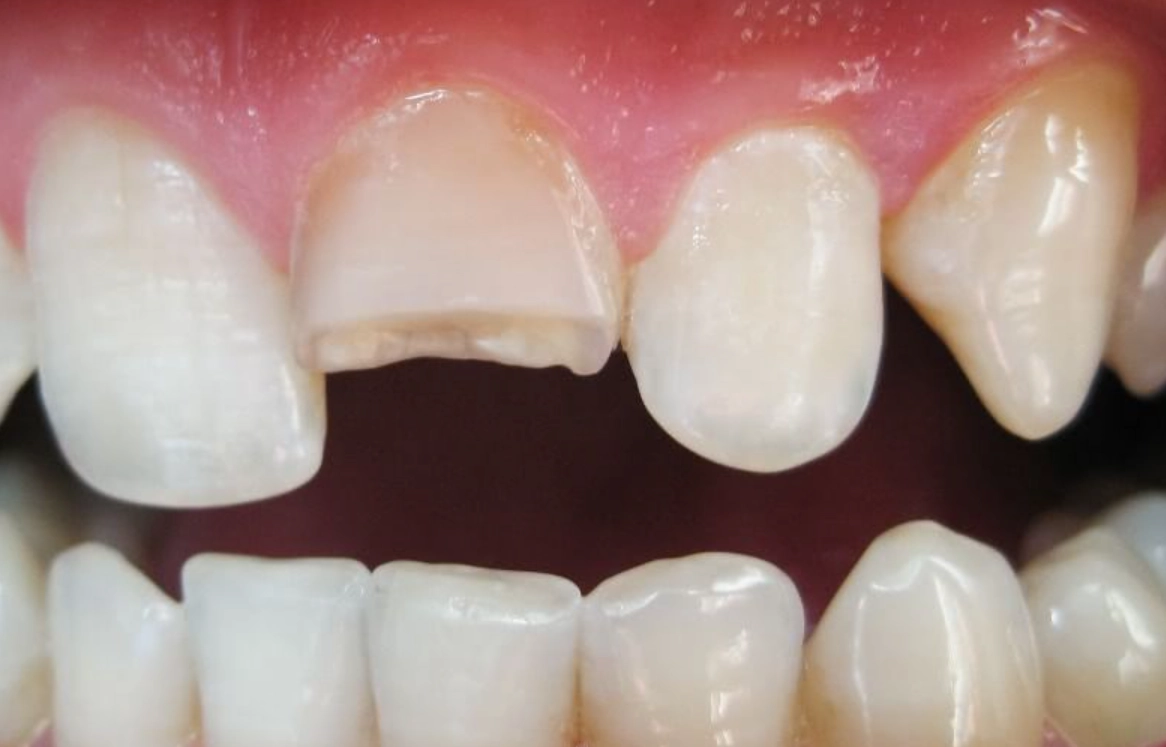

對,就是字面意思。排除生理原因永遠是第一步。夜間磨牙(學名:睡眠磨牙症)是導致牙齒斷裂的常見原因,而壓力正是磨牙的主要觸發因子之一。你可能完全沒意識到自己正在磨牙。

去看牙醫時,可以主動告知:「我最近夢到牙齒斷掉,有點擔心,可以請您幫我檢查是否有磨牙跡象或牙齒有隱裂嗎?」專業的牙醫能從琺瑯質磨損狀況判斷。如果真有磨牙問題,一副量身訂製的夜間牙套,既能保護你的牙齒,也從物理上中斷了「壓力→磨牙→夢到牙壞→更焦慮」的惡性循環。這是一個非常實際的自我照顧行動。